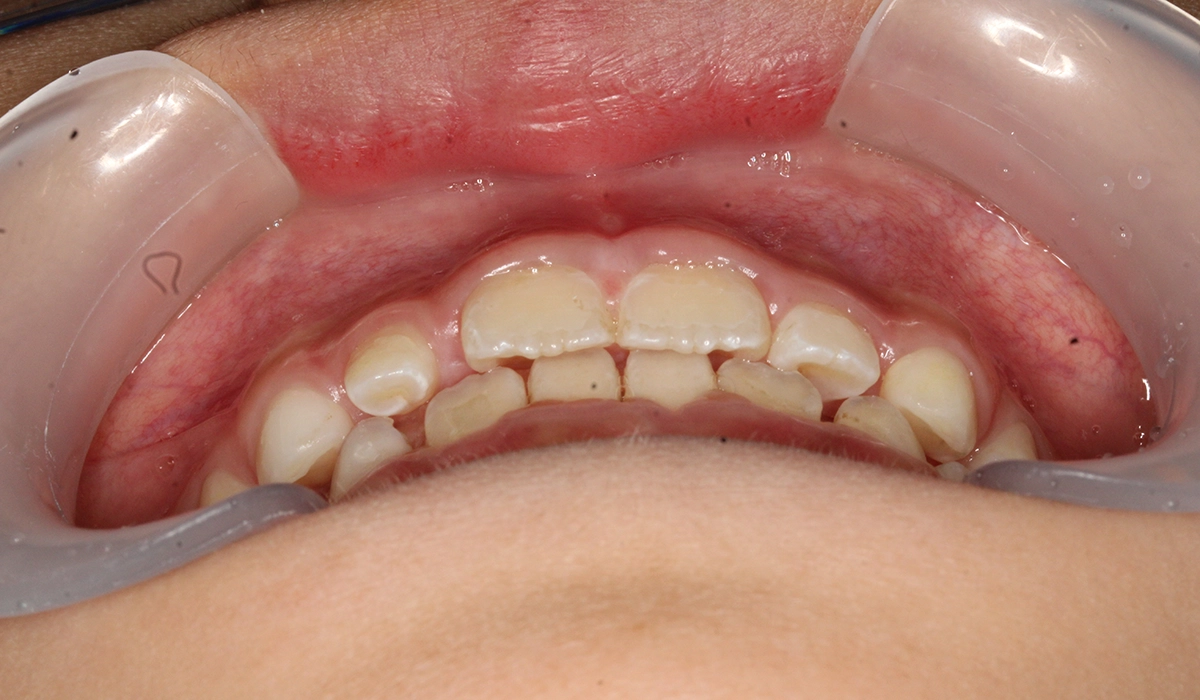

術前:正面

術後:正面